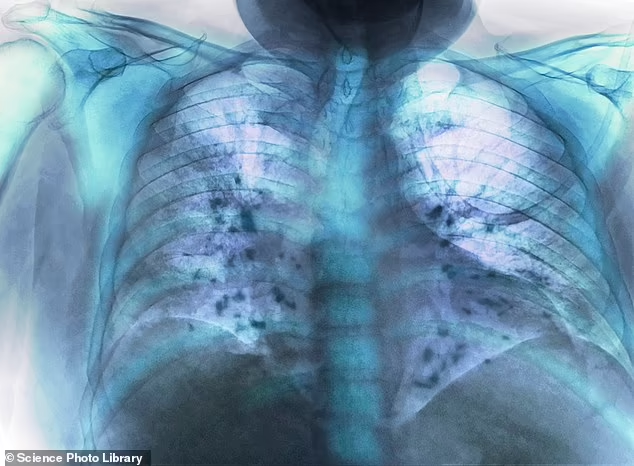

The warning comes from U.S. regulators reviewing data on vaccines that protect against respiratory syncytial virus, commonly known as RSV. This virus usually causes mild cold symptoms. However, it can be dangerous for older adults and very young babies.

According to the U.S. Food and Drug Administration, an American study found a small rise in cases of Guillain-Barré syndrome within six weeks of vaccination. This condition affects the nervous system and can lead to muscle weakness and, in severe cases, breathing problems.

RSV remains a serious seasonal threat. Each year, it hospitalizes tens of thousands and contributes to many deaths. As cases rise this winter, doctors continue to urge eligible patients to consider vaccination while staying aware of potential side effects.